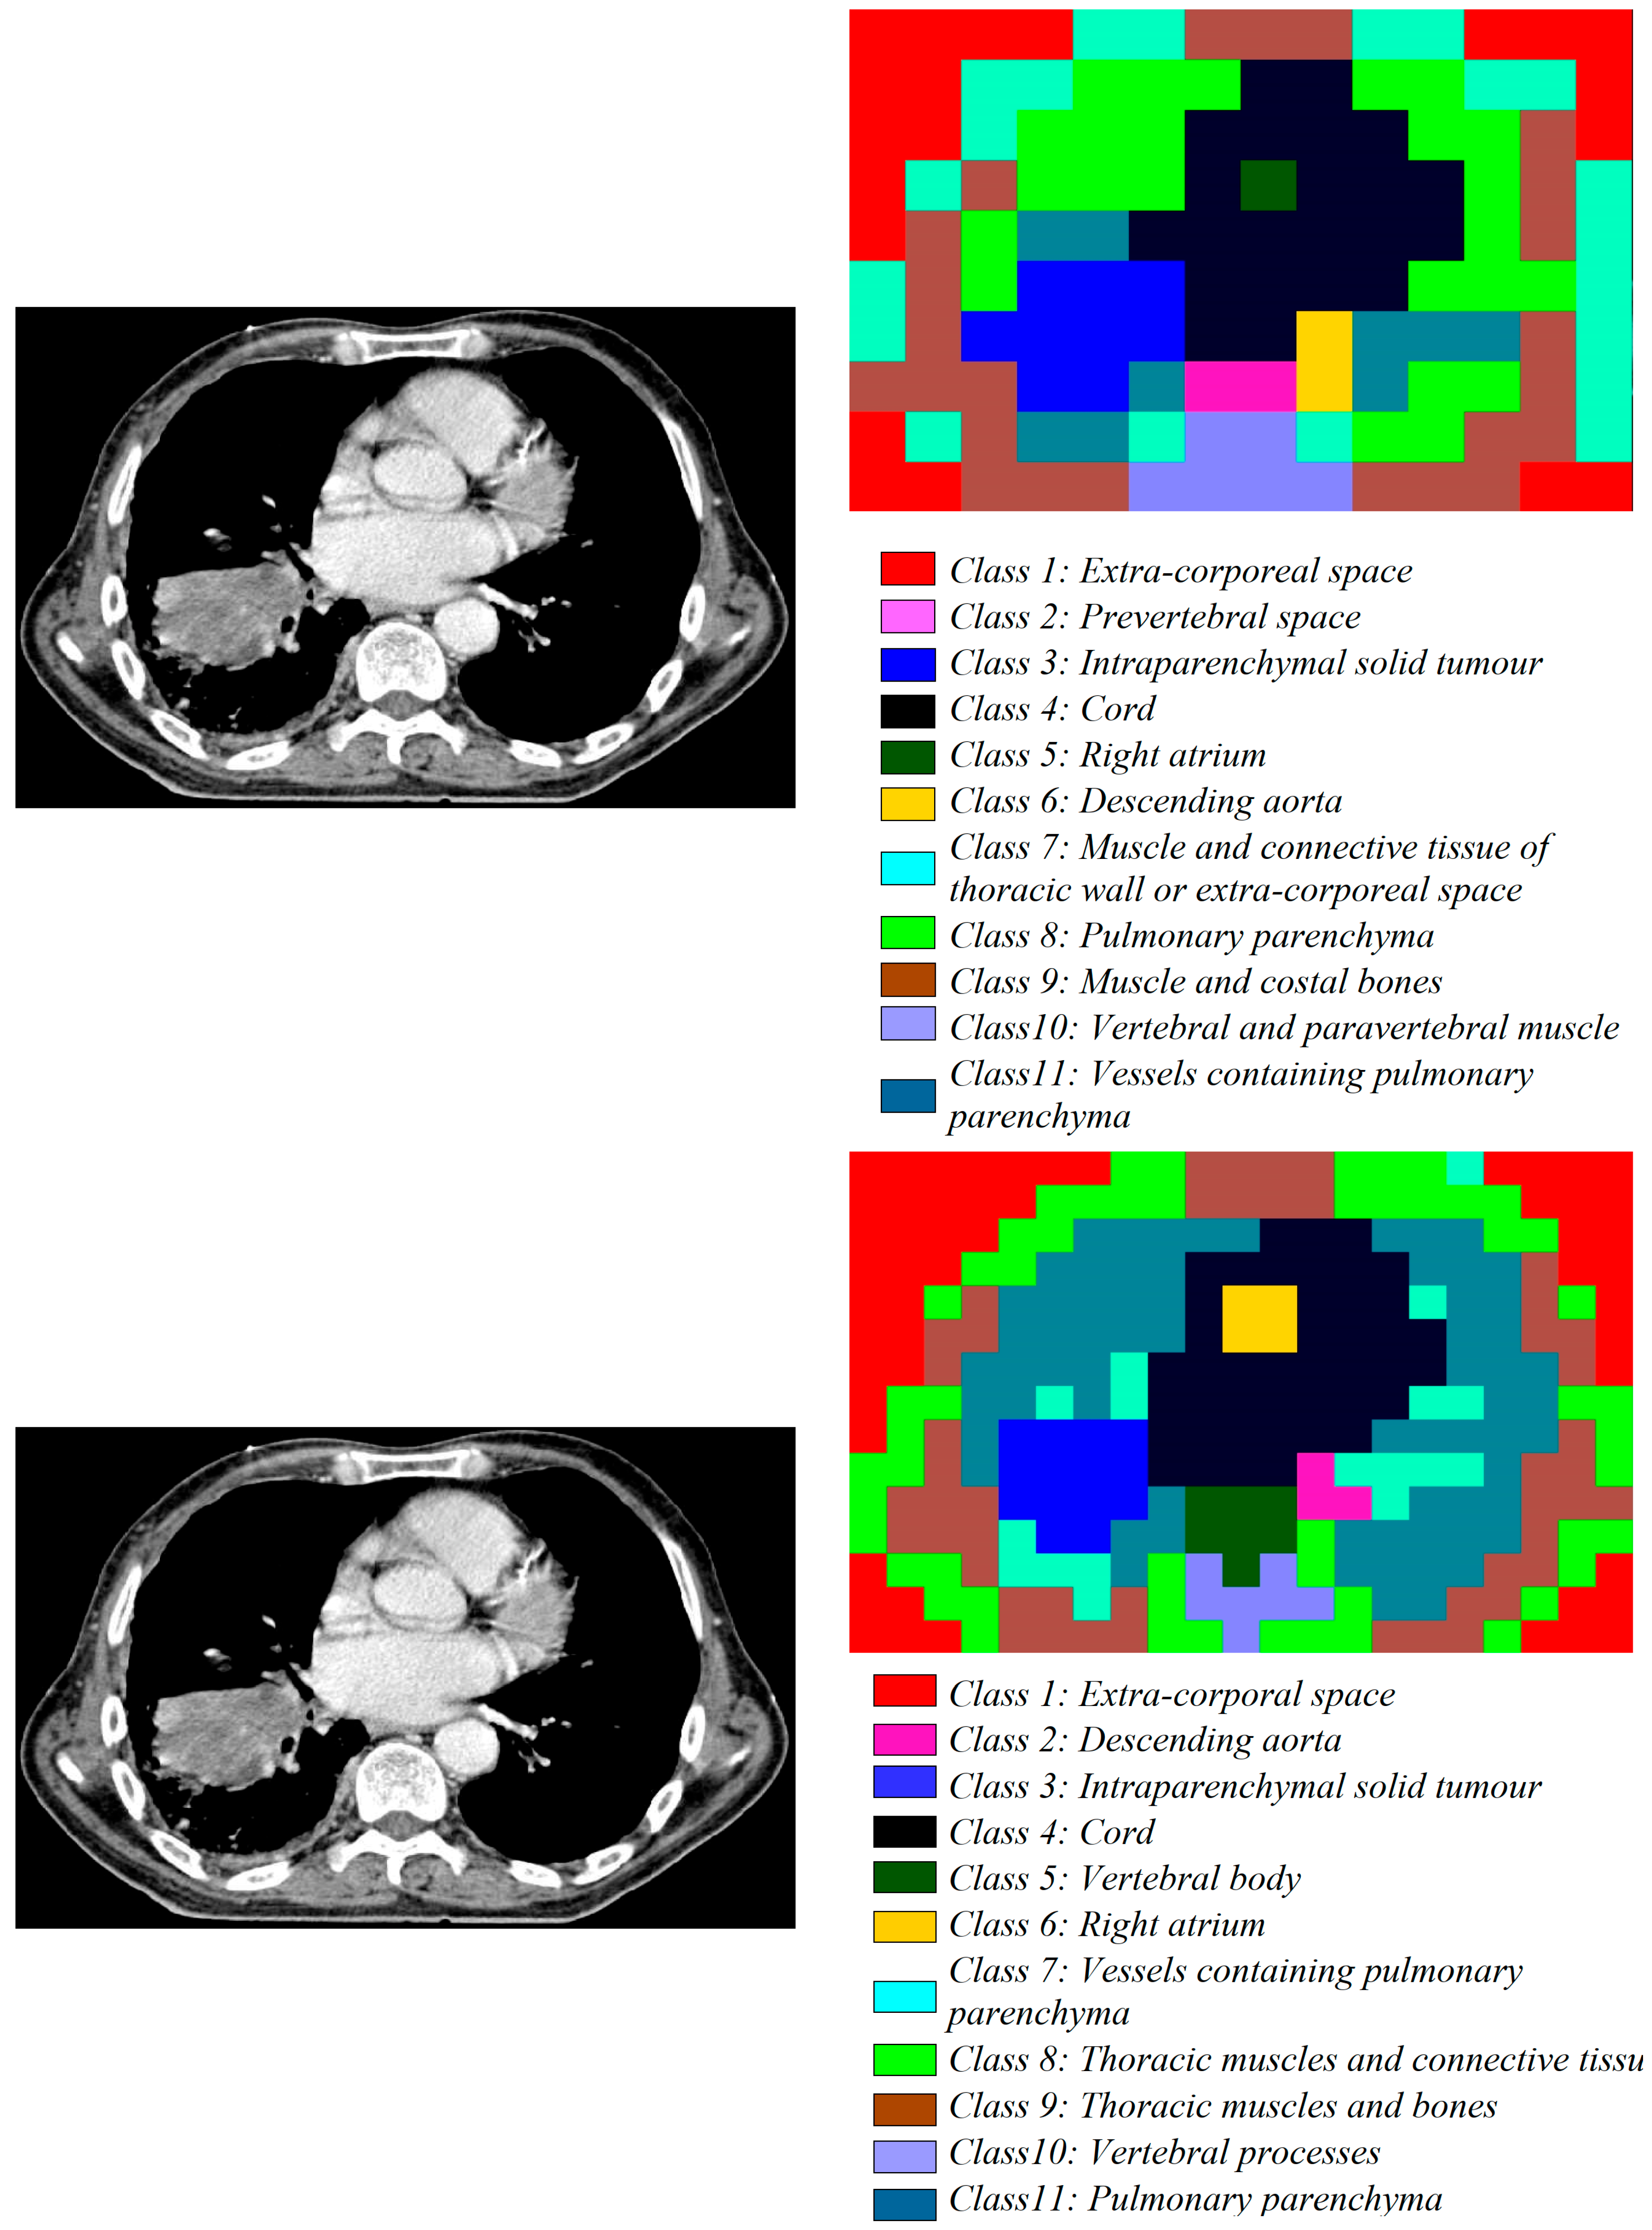

- The second dataset of images is from the patients with lung tumours; there are 11,210 CT images and 25 pathology slices collected from 6 patients. From these, we selected 10 images from 2 patients with lung adenocarcinoma. Usually, lung adenocarcinomas show an admixture of many architectural patterns such as acinar, papillary, micropapillary, lepidic, and solid growth patterns [32,33].

- The third dataset of images is extracted from a collection of 52,072 images from 422 patients with non-small cell lung cancer (NSCLC) [34]. For these patients, pre-treatment CT scans lung tumours; manual delineation by a radiation oncologist of the 3D volume of the gross tumour volume and clinical outcome data are available in [31] for the Lung1 dataset. Typically, lung cancer pathology can identify two groups of cancer cells: small cell lung cancer (SCLC) and non-small cell lung cancer (NSCLC). Then, the last ones, the NSCLC, are divided again into squamous cell cancer (SCC), large cell cancer, and lung adenocarcinoma. Finally, in situ (ISA) and invasive are the two types of lung adenocarcinoma.

3.1.2. Medical Images

| Non-small cell lung cancer | Computer tomography (CT) scan | 1/1 | avg. 1802 × 884 | 1372 × 672 | 4 × 4 | 57,624 |